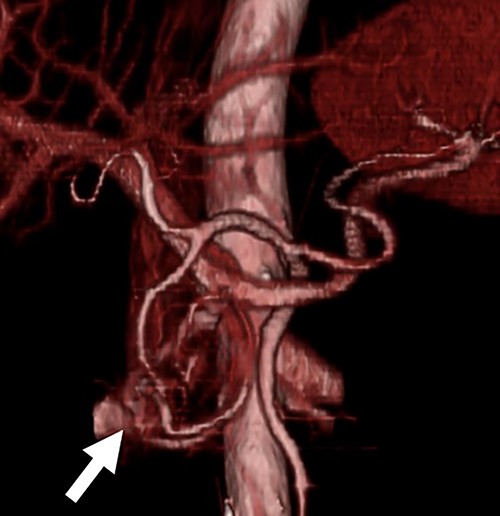

A 54-year-old man was admitted to our hospital presenting with acute upper abdominal pain. He had no family history of pancreatitis, hereditary disease or abdominal trauma; however, he had a history of habitual alcohol consumption. Blood tests showed an elevated white blood cell count (16 900/μl), serum amylase (260 U/l) and lipase (337 U/l). Contrast-enhanced computed tomography (CT) revealed meandering vessels in the pancreatic head. These vessels were enhanced in both the arterial and portal phases, while the portal vein was enhanced in the arterial phase. Swelling of the pancreatic head suggested the development of pancreatitis (Fig. 1). Three-dimensional CT revealed blood vessel communications between the arteries and veins in the pancreas (Fig. 2). Endoscopic ultrasonography (EUS) also revealed meandering vessels in the pancreatic head surrounded by low echoic lesions with diameters of 8 mm (Fig. 3). Magnetic resonance imaging (MRI) revealed flow voids and a cyst measuring 8 mm in diameter at the pancreatic head. Neither stenosis nor dilation of the main pancreatic duct was observed.

Three-dimensional CT image. The three-dimensional CT imaging showed the communication between arteries and veins in the pancreatic head (arrow).

Angiography is the definitive diagnostic modality for AVM, showing the direct communication between the arteries and veins; however, its drawback is its invasiveness. Hence, other diagnostic modalities [7, 8], including CT, MRI and EUS, are used to safely and accurately diagnose AVM of the pancreas [1–3, 13]. Particularly, three-dimensional imaging reconstructed using CT is useful for the diagnosis of AVM. The patient in our case was accurately diagnosed with an AVM of the pancreatic head using contrast-enhanced CT and EUS without angiography.